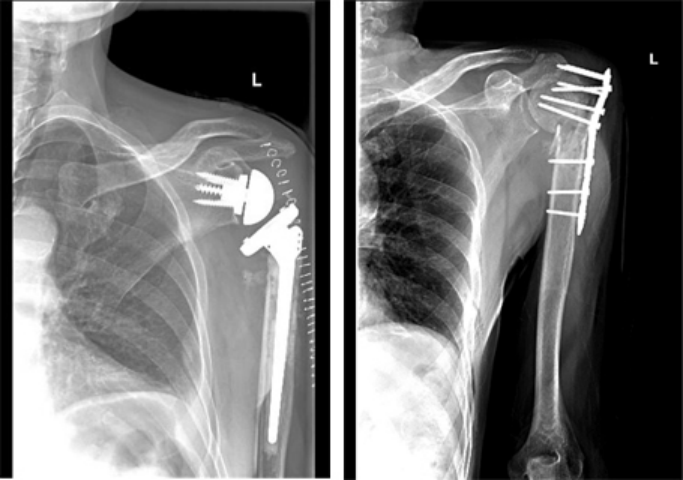

4.关节置换术

老年人关节内骨折合并骨质疏松症时,软骨下骨质量差,骨折块易嵌入关节面,解剖复位困难,骨折复位在下地负重或关节活动时难以维持,因此内固定治疗效果不佳。此时可酌情选择关节置换治疗,能够获得更好的预后。当骨折未累及关节面,但存在股骨头缺血性坏死风险时,例如股骨头下骨折或肱骨近端骨折,关节置换术的疗效于内固定[27][28][29]。随着反肩关节置换术的出现,越来越多的骨科医生选择关节置换术治疗复杂的肱骨近端骨折,获得了良好的治疗效果而肘关节置换术已成为复杂骨质疏松性肱骨远端骨折的常规治疗手段,临床研究也验证了其优良且可靠的治疗效果[28]。因此,当骨质疏松性骨折骨质量差,骨折碎片较小时,人工关节置换术应首先考虑。